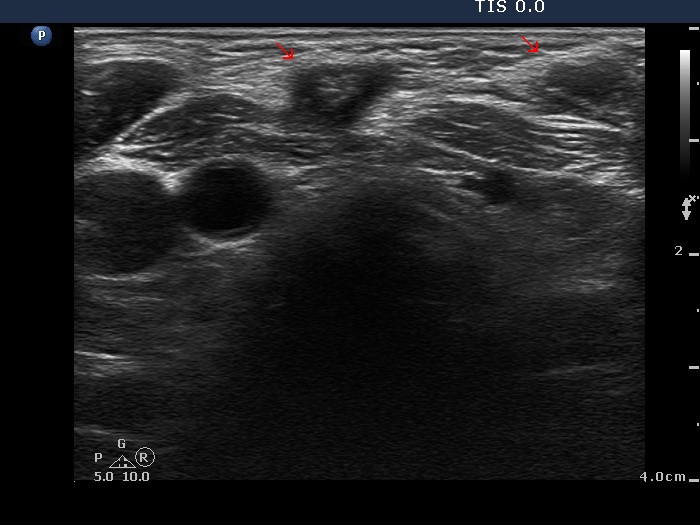

Granulation around surgical thread (cytological diagnosis) - case 1475

There are two granulations both in the left, horizontal and in the right, longitudinal images (arrows). The shape of the masses is irregular. The granulations are hypoechogenic and have one or more echonormal foci.